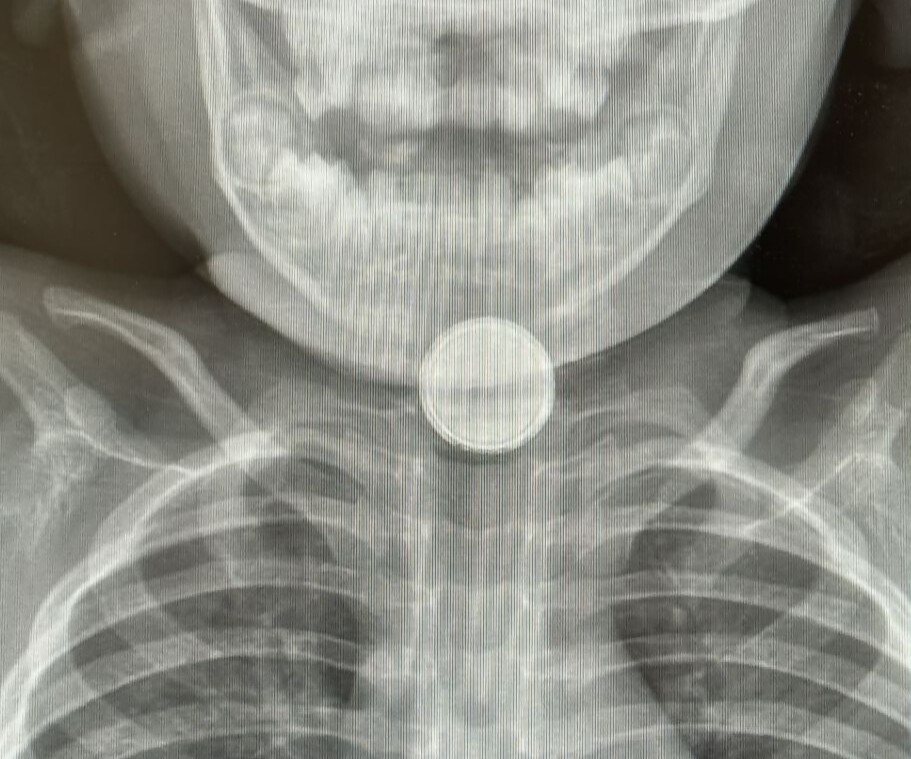

במרכז הרפואי סורוקה בבאר שבע מדווחים על עלייה חדה במספר מקרי בליעת סוללות בקרב ילדים – תופעה מוכרת ומסוכנת במיוחד בגיל הרך. בשבועות האחרונים הגיעו לבית חולים סבן לילדים מספר ילדים כשהם סובלים מפגיעות פנימיות קשות בעקבות בליעת סוללות קטנות, המוכרות מסוללות כפתור המשמשות שלטים, צעצועים, מפתחות רכב ועוד.

המקרה החמור ביותר שנרשם לאחרונה היה של פעוט בן שנתיים שהובהל לחדר ההלם כשלושה ימים לאחר שבלע סוללה – באיחור מסוכן. הוא נזקק להתערבות חירום בחדר ניתוח, ועדיין לא ברורה מידת הנזק שנגרם לוושט ולכלי הדם הסמוכים. במקרה אחר, ילדה בת 7 פונתה תוך זמן קצר אך כבר הספיקה להיפגע – החומר הכימי החל להתפשט באזור כלי הדם, והצוות הרפואי מעריך כי תזדקק לניתוח בהמשך.

בליעת סוללות נחשבת לאירוע רפואי חירומי: סוללה שנתקעת בוושט עלולה לגרום לנזק בלתי הפיך תוך דקות. החומר הכימי שבתוכה חודר לרקמות, ועלול להמשיך להתפשט גם זמן רב לאחר הוצאת הסוללה – לעיתים אף למעלה מחודש.